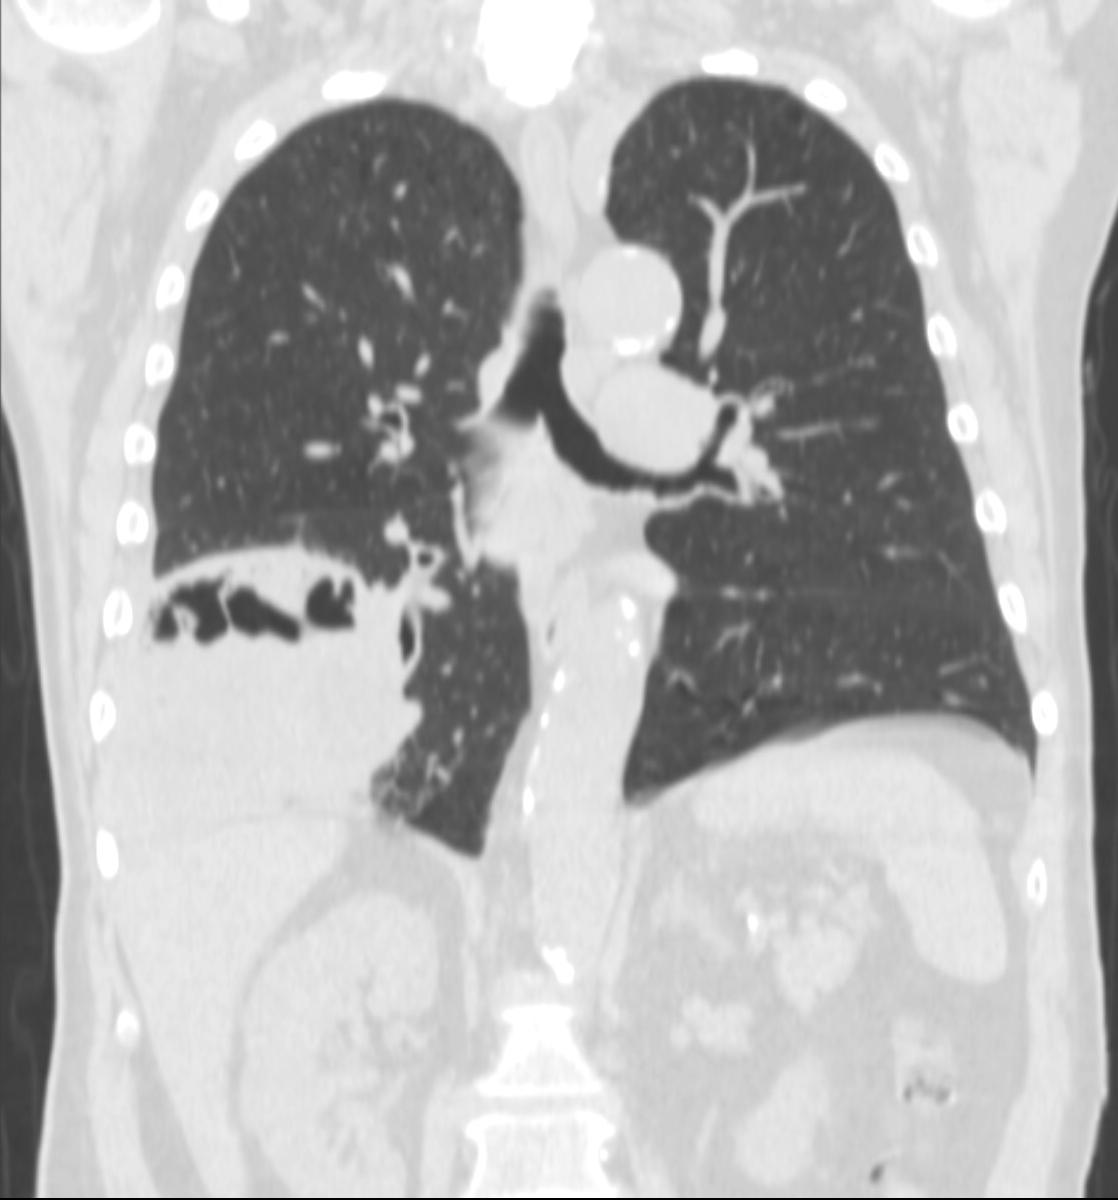

3b: Multiple lung metastasis, CT lung window (axial, coronal reformat)

Image

3c, coronal reformat

70 year old man, colon tumor.

Radiograph: Bilateral extensive, confluating patchy-nodular shadowing with diffuse reticular pattern. The diaphragm contour is partially blurry bilaterally: lymphangiosis carcinomatosa.

CT: Numerous 1-6 cm round and irregular, lobulated-spiculated contrast enhancing lesions in both lungs, everywhere sporadically.